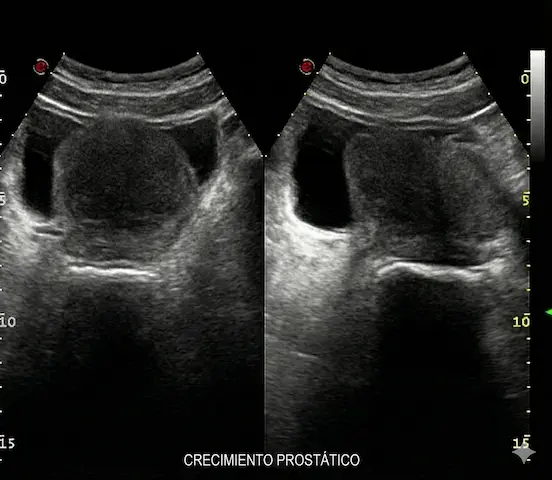

• Ecografía Urológica: Permite ver el tamaño exacto de la próstata en gramos y calcular orina atrapada (Residuo Postmiccional).